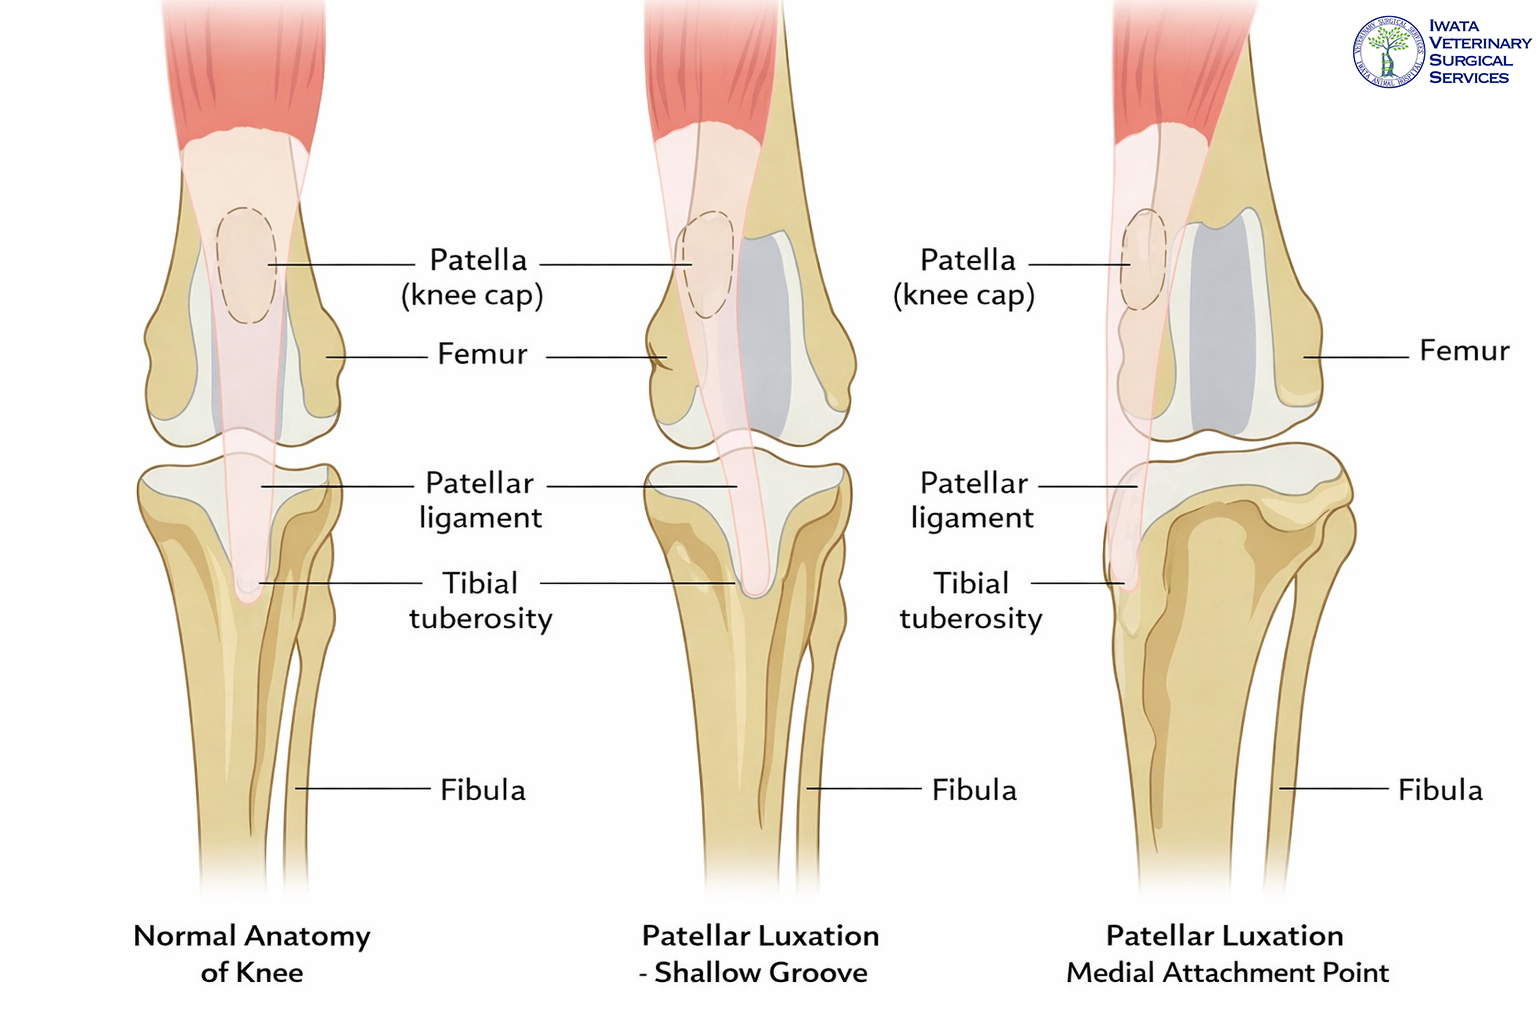

病態・原因

膝蓋骨内方脱臼は、膝蓋骨が滑車溝から脱臼し、内側に変位することで疼痛や運動機能障害が生じる整形外科疾患です。発症要因について、いわゆる「先天性」と表現されることがありますが、厳密には出生後の成長過程で形成される発育性疾患と考えられています。

生まれつき膝蓋骨が外れているわけではなく、もともと存在する骨格の素因が、成長に伴って膝関節周囲の変形を進行させ、最終的に膝蓋骨が内側へ外れやすくなります。

主な異常としては、以下が挙げられます。

- 大腿骨や脛骨の変形

- 大腿四頭筋機構のアライメント異常

- 脛骨粗面の内側偏位

- 脛骨の内旋

- 大腿骨滑車溝の浅さ(滑車低形成)

- 大腿骨内側顆の低形成

正常では、膝蓋骨が滑車溝にはまり込むことで、成長期に滑車溝の深さが保たれます。しかし、早期から膝蓋骨が正常な位置にない場合、滑車溝が十分に発達せず浅くなるため、さらに脱臼しやすくなるという悪循環が生じます。また、このような骨格異常には遺伝的背景が関与すると考えられており、繁殖には慎重な判断が必要とされています。